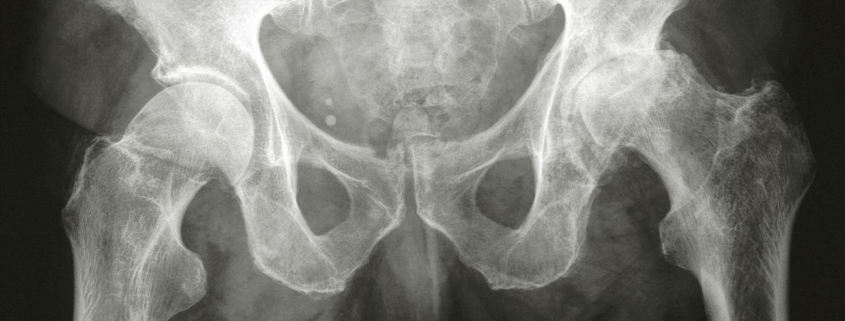

A conclusive diagnosis of hip arthritis is made by a medical professional after considering the patient’s symptoms, medical history, a physical exam, and diagnostic tests. The tests commonly used include X-ray imaging to see changes in the joint, and blood tests, especially for rheumatoid arthritis. An MRI (Magnetic Resonance Imaging) may be ordered in some cases for a more detailed view.